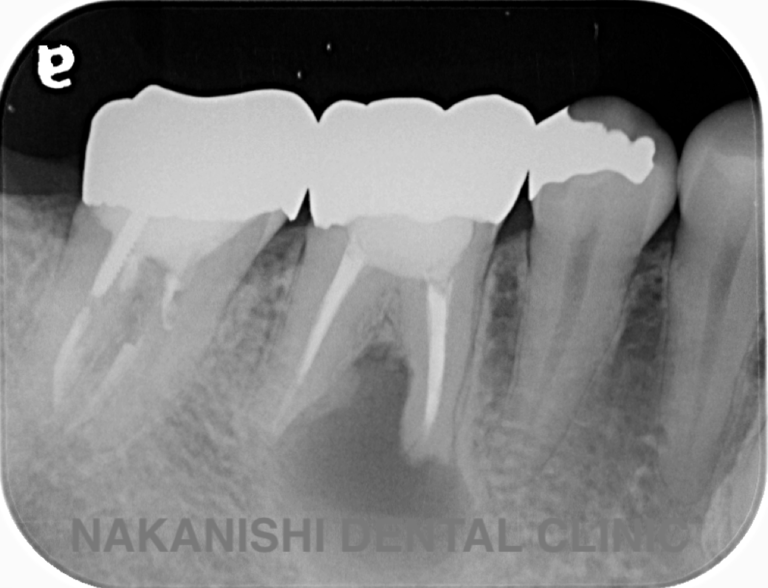

case 3.

治療前

治療後

| 主訴 | 左下奥歯が痛い、歯ぐきの腫れ。 前医で抜歯を提案されたがセカンドオピニオン希望でご来院。 |

|---|---|

| 治療期間 | 約半年(6か月) |

| 治療費 | 約5万円 |

| 治療内容 | 前医ではラバーダム不使用であったため、ラバーダム、マイクロスコープ下にて根管治療を施術。 痛みは消失したが腫れは治らなかったため、意図的再植を行い腫れは消失した。治療後のレントゲンは意図的再植後3年経過したもの。 |

| 治療のリスク | マイクロスコープやCTを使用し、可能な限り精密な根管治療を行っていますが、歯根の形態や病変の大きさ、過去の治療履歴などにより、治癒が得られない場合があります。 また、治療後に再感染や歯根破折が生じることもあり、その場合は再治療や抜歯が必要となることがあります。 治療結果には個人差があり、すべての症例で同様の経過を保証するものではありません。 |